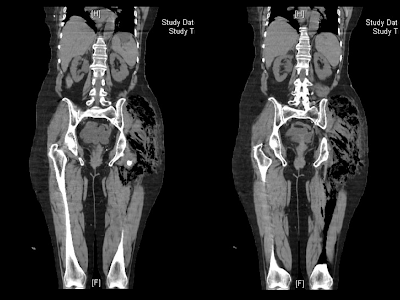

Entre

las 7h y las 10h, la paciente presenta progresivo empeoramiento clínico con

inestabilidad hemodinámica, hematuria, ictericia y crepitantes a palpación en

muslo izquierdo y Fosa iliaca izquierda. Se realiza nuevo control gasométrico arterial

aire ambiente (pH 7.39, pCO2 17.40, pO2 75.1, CO3H 10.4, Exceso base art -11.5,

láctico 14mmol, SatO2 95.4%), TC toraco-abd-pélvico urgente y se solicita

valoración por UCI decidiéndose traslado a dicha unidad.

- Fascitis/

Miositis nerotizante. Gangrena gaseosa - Se

- Ante

la sospecha clínica, siendo el cuadro típico dolor muy intenso, fiebre y

presencia de gas en tejido blando visto en pruebas de imagen (Rx, TC o RMN), es

necesario actuar de manera precoz mediante desbridamiento